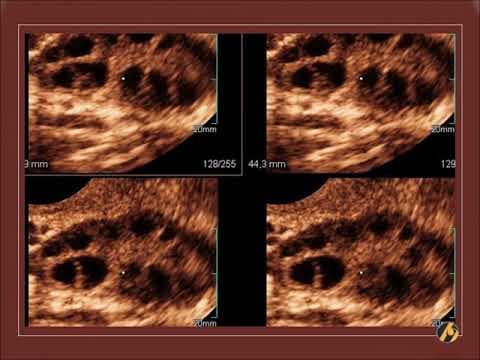

Pcos-ultrazvucne-slike